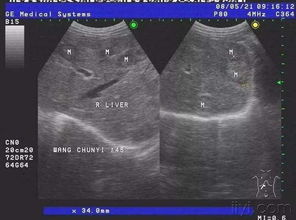

B超,全称为超声波检查,是一种无创、无辐射的医学检查方法。它通过向人体内部发射超声波,然后接收反射回来的信号,从而形成图像,帮助医生了解人体内部器官的结构和功能。

B超在医学领域有着广泛的应用,如妇科、产科、心血管、腹部等。它就像一位侦探,能够揭示人体内部的秘密。